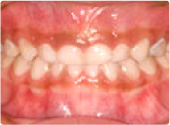

メタルクラウンとオールセラミックス比較

治療前

治療後

オールセラミックスにすることで歯茎の色まできれいになります。